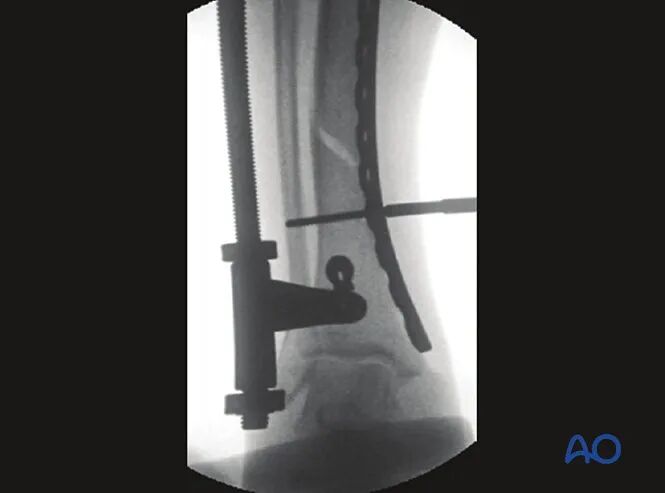

大型牵开器或外固定架

若手法牵引失败,可采用大型牵开器进行闭合复位。于骨折远近端骨折块分别置入斯氏针,旋转螺纹杆螺母,通过针体施加牵开力。

若计划行内侧接骨板固定,牵开器应置于患肢前方。

:warning:️注意:斯氏针需置入同一解剖平面,确保牵开器安装后胫骨旋转力线正常;牵开器就位后,旋转力线难以调整。

:warning:️注意事项:若牵开器施加的牵拉力过大,骨折端可能出现成角畸形,且畸形凹侧与牵开器位置相反。

如牵开器置于内侧时,易导致骨折端外翻畸形;置于前方时,易造成骨折端屈曲畸形(前侧成角)。

术者一旦发现该问题,可通过调整牵开器针夹位置予以矫正。

处理方案:通过调整牵开器或外固定架的针体位置,纠正成角畸形。牵开器撑开过程中,软组织张力分布不均,会引发骨折端成角,且凹侧朝向与牵开器位置相反。

如图所示,将牵开器针夹调整至成角状态,可使骨折端形成后侧成角;随着牵拉力的施加,肢体长度恢复,后侧成角畸形随之矫正。